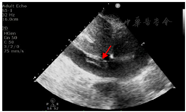

继续予患者有创呼吸机辅助通气,因血流动力学不稳定(低血压、氧饱和度持续<90%),予置入ECMO辅助循环,同时予抗感染、抑酸、抗凝等治疗。针对暴发性心肌炎,予糖皮质激素冲击(甲基强的松龙500 mg/d,共2 d)和丙种球蛋白(20 g/d,共4 d)调节免疫。经上述治疗后患者血流动力学稳定,血压130~140/60~70 mmHg,血乳酸1~2 mmol/L,氧分压90~100 mmHg。监测EOS和hscTnI最初呈下降趋势,但入心内监护室后第3日EOS和hscTnI较前再次升高,故第3日将甲基强的松龙加至1000 mg,其后监测EOS和hscTnI仍继续升高。考虑患者暴发性心肌炎继发于高嗜酸性粒细胞增多综合征(hypereosinophilic syndromes,HES)可能性大,请血液科会诊后,筛查原发性HES、继发性HES和嗜酸性肉芽肿性多血管炎(查ANCA阴性,不支持)。原发性HES方面:行骨髓穿刺和活检,并送检全外显子测序和融合基因,包括FIP1L1-PDGFRA融合,PDGFRB,FGFR1,PCM1-JAK2融合等,均为阴性。继发性HES方面,查血白介素-5(IL-5)未见升高(糖皮质激素治疗2 d后),外送多种寄生虫抗体阴性,血IgE不高,全身浅表淋巴结超声未见异常,入院后曾行胸部CT和腹部超声未见实体肿瘤证据。患者无原发性和继发性HES证据,考虑为特发性HES,但对糖皮质激素反应不佳、治疗相对困难。根据EOS计数,逐渐加用羟基脲、芦可替尼、环磷酰胺和依托泊苷,并将甲基强的松龙逐渐减量,患者EOS和hscTnI均呈逐渐下降趋势。患者心功能亦逐渐恢复,ECMO辅助1周后复查超声心动图,左心室射血分数恢复至60%,予撤除ECMO。撤除ECMO后复查超声提示下腔静脉条状血栓(图1),继续抗凝治疗。但患者撤除ECMO、停用镇静药物后意识状态界于醒状昏迷至微小意识状态之间,可自主睁眼,呼之不应,四肢无肌力和肌张力,复查头颅MRI提示双侧多发脑梗死,较前明显增多,梗死部位以分水岭为主(图2)。患者意识持续不恢复,予气管切开、人工鼻通气,转回神内科进一步治疗。